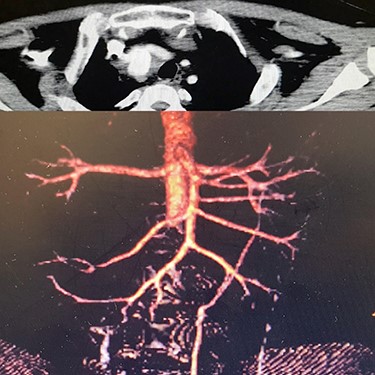

Case 3 – A 44-year-old man, known case of BD, who underwent open surgery for right common iliac artery aneurysm 1 year ago. The patient was referred to our hospital with a huge pulsatile neck mass. The right femoral artery pulse was absent in physical examination. CTA showed the iliac graft was thrombosed, but his lower limb did not have symptoms of ischemia. Corticosteroid therapy was prescribed before starting the procedure. In addition, a left carotid artery aneurysm was identified (Fig. 4A), so a stent-graft was inserted in the left common carotid (Fig. 4B). The pulsation and bruit of the mass disappeared immediately after the procedure and patient was discharged without complications. After 1-year follow-up, there was no sign of pseudo-aneurysm and the stent-graft was open.

(A) Carotid angiography before stent-graft placement (left), (B) after stent-graft placement (right).